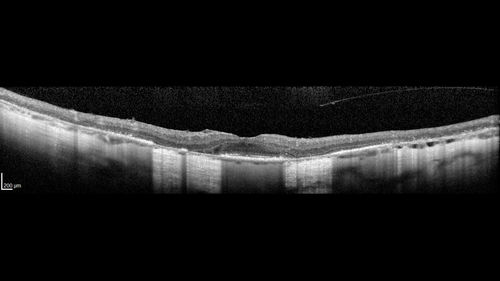

Retinitis Pigmentosa - RP1 Mutation

78 year old man: 20/32 OD and 20/50 OS - RP1 Gene is Bad -- > RP with Novel Amino Acid Change in GLY723Stop sequence of the RP1 gene - consistent with AD RP